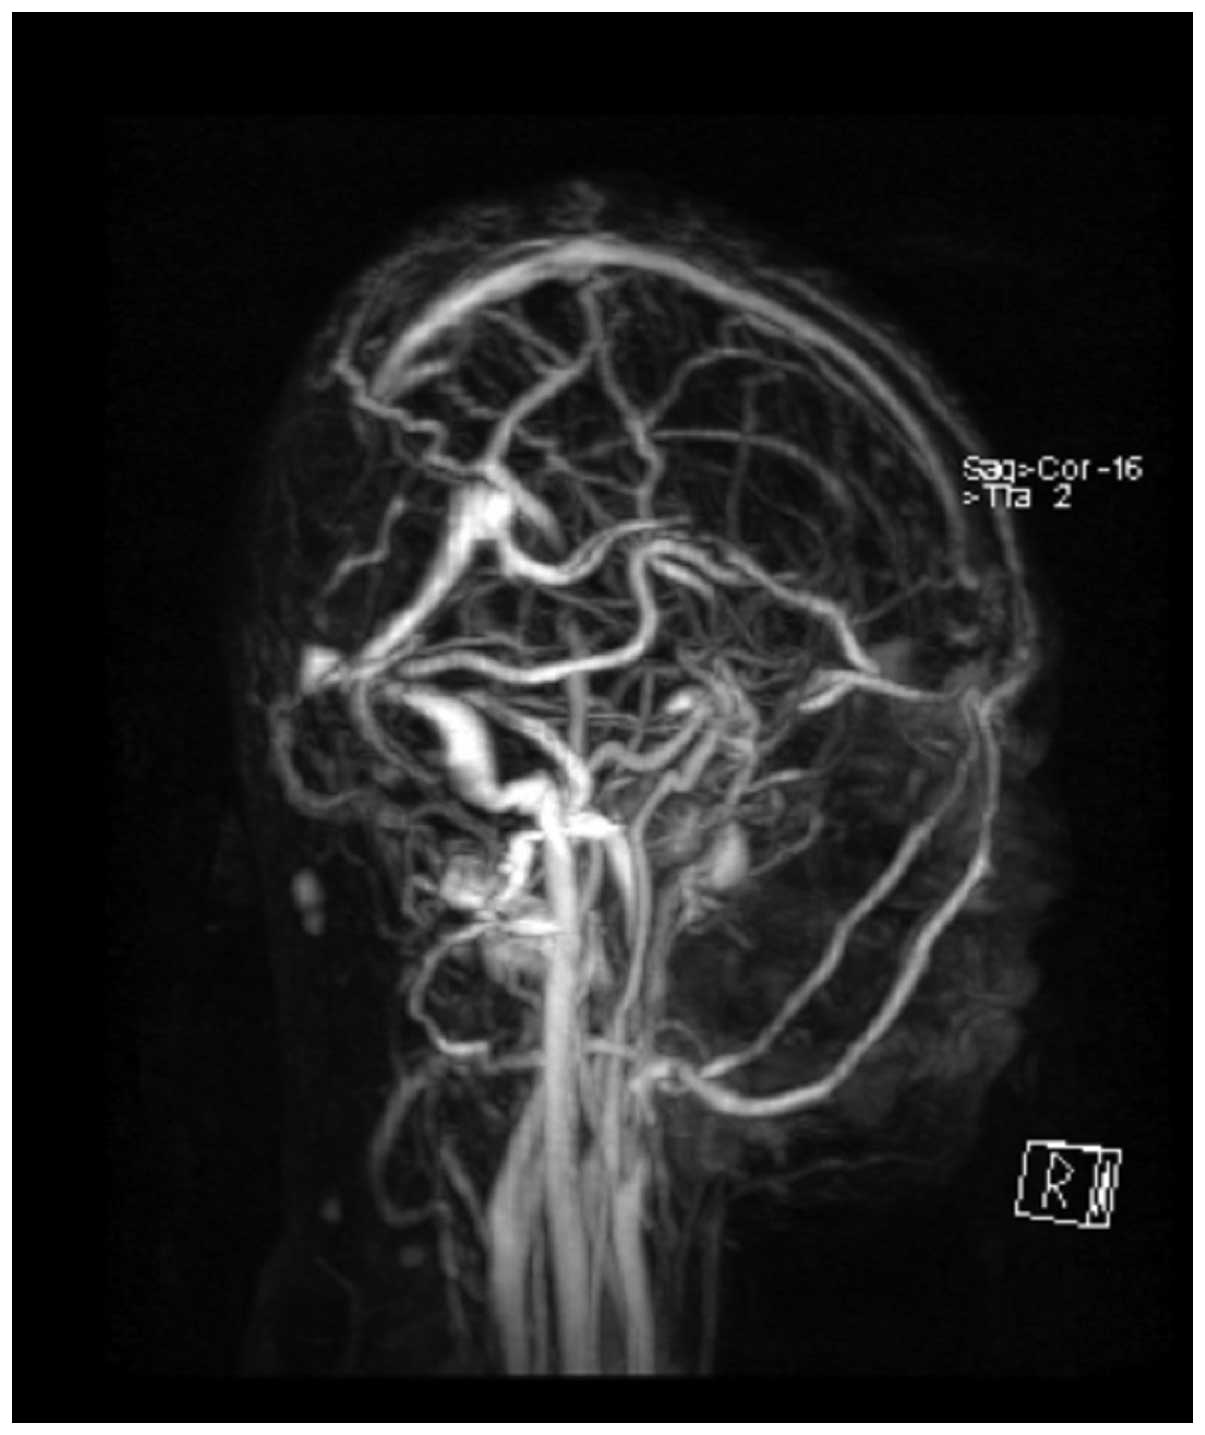

CT imaging (SOMATOM Sensation 16; Siemens Healthcare GmbH, Erlangen, Germany) demonstrated an oval-geographic, osteolytic lesion within the squamous part of the occipital bone, with a well-demarcated intracranial, calvarial and extracalvarial soft tissue mass (Fig. 1). MRI (Signa HDxt 1.5T; GE Healthcare, Fairfield, CT, USA) revealed a focal, 5.0×4.5×3.5-cm mass with bilateral occipital lobe invasion. The mass exhibited hypo- and iso-signal intensity on T1-weighted imaging and mixed-signal intensity on T2-weighted imaging. Gadolinium-enhanced images revealed prominent perilesional enhancement, particularly in the region adjacent to the brain. Irregular hypointense areas within the mass were visible on T2-weighted imaging, without obvious enhancement (Fig. 2). MR venography (Sonata 1.5T; Siemens Healthcare GmbH) was also applied to evaluate the cerebral vein system. MR venography and MRI indicated that the superior sagittal sinus and torcular herophili had been invaded, and associated vasogenic cerebral edema due to mass effect was noted (Figs. 2 and 3).

Figure 3.

Brain magnetic resonance venography demonstrated a filling defect in the superior sagittal sinus and torcular herophili.

Radiological findings, although scarce in the literature, were distinctive in the current case. The imaging findings demonstrated a well-defined, heterogeneous, intracranial, calvarial and extracalvarial mass with bone destruction. The osteolytic lesion presented sharp borders, a lack of bony sclerosis and a paucity of periosteal reaction. The adjacent brain and venous sinus were invaded. These appearances may reflect the malignant biological behavior of the tumor. On T2-weighted MRI without enhancement, irregular areas of low signal intensity were visible, a characteristic which may be observed in areas of decreased cellularity and dense fibrous tissue or collagen deposition (10). High signal intensity on T2-weighted images without enhancement is considered to indicate necrosis (11,12). Intense perilesional enhancement of the tumor-adjacent brain region on gadolinium-enhanced MR images may be associated with histopathological changes, which include cellular and vascular proliferation, peritumoral desmoplastic reaction and inflammatory cell infiltration. This enhancement pattern may also be indicative of malignant tumors (13). Therefore, in the current case, imaging findings successfully suggested a tumor of high malignancy containing necrosis and fibrous tissue.